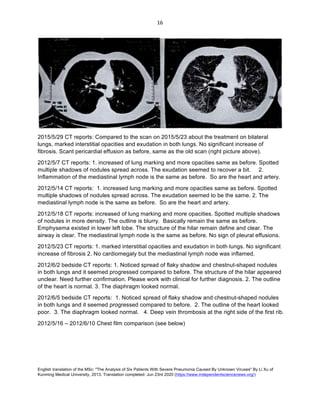

2015/5/29 CT reports: Compared to the scan on 2015/5/23 about the treatment on bilateral

lungs, marked interstitial opacities and exudation in both lungs. No significant increase of

fibrosis. Scant pericardial effusion as before, same as the old scan (right picture above).

2012/5/7 CT reports: 1. increased of lung marking and more opacities same as before. Spotted

multiple shadows of nodules spread across. The exudation seemed to recover a bit. 2.

Inflammation of the mediastinal lymph node is the same as before. So are the heart and artery.

2012/5/14 CT reports: 1. increased lung marking and more opacities same as before. Spotted

multiple shadows of nodules spread across. The exudation seemed to be the same. 2. The

mediastinal lymph node is the same as before. So are the heart and artery.

2012/5/18 CT reports: increased of lung marking and more opacities. Spotted multiple shadows

of nodules in more density. The outline is blurry. Basically remain the same as before.

Emphysema existed in lower left lobe. The structure of the hilar remain define and clear. The

airway is clear. The mediastinal lymph node is the same as before. No sign of pleural effusions.

2012/5/23 CT reports: 1. marked interstitial opacities and exudation in both lungs. No significant

increase of fibrosis 2. No cardiomegaly but the mediastinal lymph node was inflamed.

2012/6/2 bedside CT reports: 1. Noticed spread of flaky shadow and chestnut-shaped nodules

in both lungs and it seemed progressed compared to before. The structure of the hilar appeared

unclear. Need further confirmation. Please work with clinical for further diagnosis. 2. The outline

of the heart is normal. 3. The diaphragm looked normal.

2012/6/5 bedside CT reports: 1. Noticed spread of flaky shadow and chestnut-shaped nodules

in both lungs and it seemed progressed compared to before. 2. The outline of the heart looked

poor. 3. The diaphragm looked normal. 4. Deep vein thrombosis at the right side of the first rib.

2012/5/16 – 2012/6/10 Chest film comparison (see below)